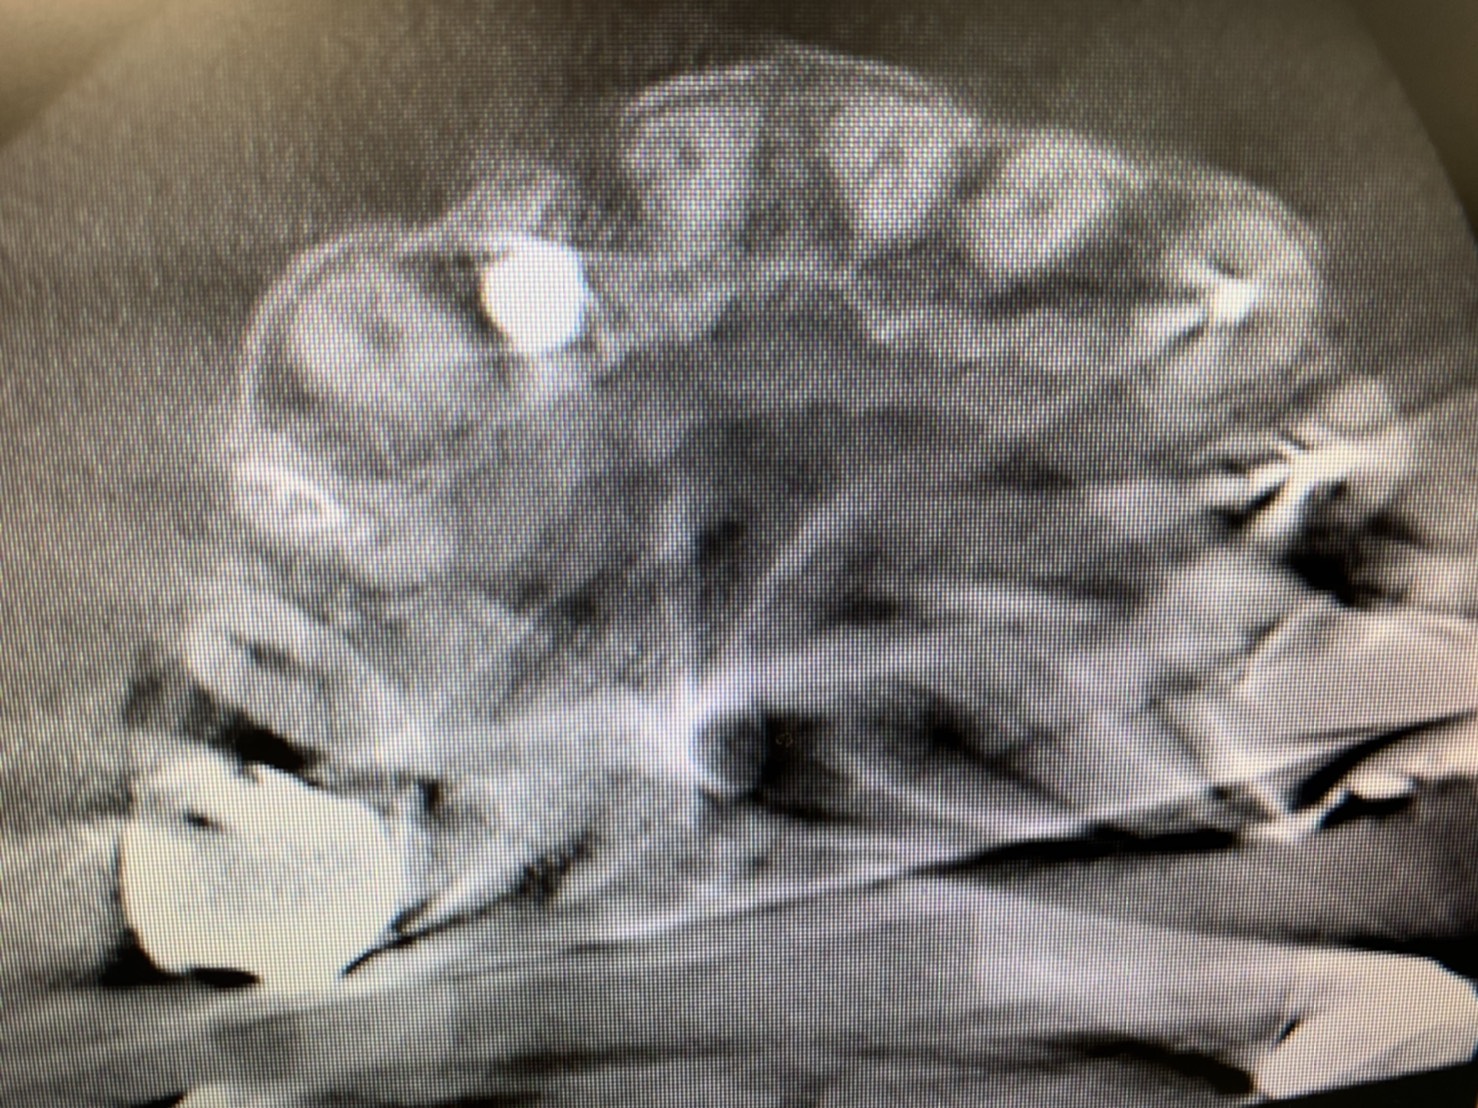

(インプラント埋入後CT画像)

本日は最長18ミリインプラント体埋入

低位舌側埋入で良いですね!(埋入位置は様々な理由で事前に狙う位置を確保するのは難しい)(コンピュータの解析だけに頼らず現場に即した対応が大切)

生着値は70.68とギリギリボーダーですので、即時はやめて5ミリのヒーリングで終了